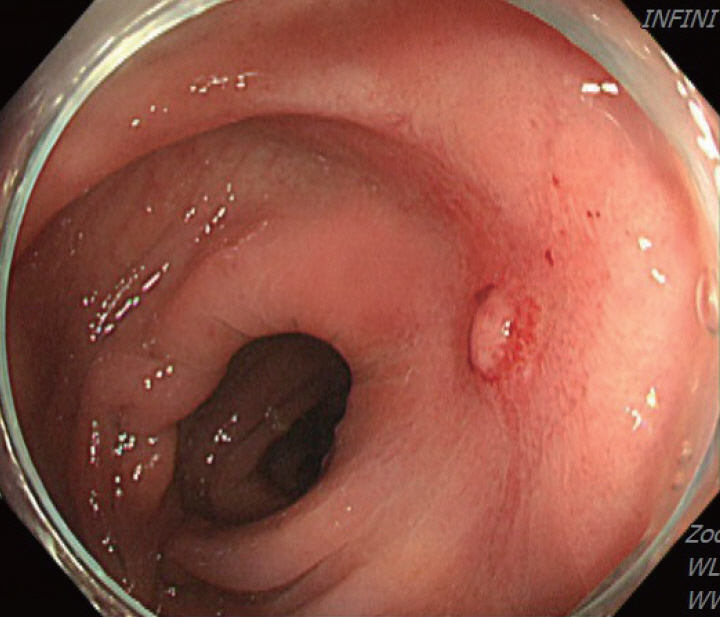

Figure 2.

Initial colonoscopy showing an irregularly shaped gross margin of the ulcer.

A 70-year-old male underwent sigmoidoscopy after a routine computed tomography (CT) examination, which showed thickening of the sigmoid wall (Fig. 1). Sigmoidoscopy revealed a colonic ulcer, and a biopsy was performed. The lesion was identified as a tubular adenoma; therefore, the patient was referred to the gastroenterology department for repeat biopsy and additional tests. The patient’s medical history included high blood pressure and alcoholic hepatitis. His social history showed that he drank 0.5-1.0 bottle of soju daily and was never a smoker. Information regarding his family history was excluded from the study. The patient had no gastrointestinal symptoms such as abdominal pain or diarrhea, and physical examination findings were unremarkable. Although the biopsy showed a tubular adenoma, the initial colonoscopy indicated that the gross margin of the ulcer was irregularly shaped (Fig. 2), raising suspicion for malignancy. Therefore, despite being asymptomatic, the patient was informed, and another colonoscopy was performed 2 months later. The follow-up examination revealed a scarred sigmoid ulcer located 30 cm from the anal verge, which seemed to have improved compared with the previous findings. Re-biopsy demonstrated features consistent with a simple ulcer (Fig. 3). Accordingly, we concluded that this was a benign colonic ulcer with an inflammatory and ischemic cause rather than cancer, and a follow-up CT scan was sche-duled 1 month later. At the follow-up visit 1 month later, the patient complained of abdominal discomfort after eating for a week, which had not occurred before. He denied having fever, chills, nausea, or vomiting. A subsequent abdominal CT scan showed an approximately 9-cm cavitary lesion abutting the sigmoid colon and urinary bladder dome in the small intestine (Fig. 4). This was accompanied by diffuse nodular omentomesenteric infiltration and peritoneal thickening with small ascites. Based on these findings, the patient was suspected to have a malignant tumor, such as scirrhous carcinoma, inflammatory bowel disease, peritoneal carcinomatosis, or peritonitis, and was referred to a surgeon for surgical treatment. The patient was hospitalized immediately. On admission, the patient complained of abdominal discomfort after eating, and mild generalized abdominal tenderness was noted on physical examination. He was hemodynamically stable. Laboratory testing revealed high white blood cell count of 11.45 × 103/μL (normal range, 4.0-10.0 × 103/μL) with a differential of 67.6% neutrophils (normal range, 38.0-75.0), normal hemoglobin of 16.1 g/dL (normal range, 13.0-17.0), normal platelet count of 151 × 103/μL (normal range, 150-400 × 103/μL), and slightly elevated C-reactive protein level of 7.69 mg/L (normal range, 0.0-5.0). Serum electrolyte and kidney function test results were normal. On the 3rd day of hospitalization, the patient underwent laparoscopic small bowel resection. Immunohistochemical analysis of the resected tissue showed positive staining for CD3, CD4, CD8, CD56, and CAM 5.2 (epithelial marker), and a negative staining for CD10, CD20, CD21, and CD30 (Fig. 5). Histopathological evaluation revealed infiltration by small- to medium-sized T-cell with prominent epitheliotropism, consistent with MEITL. The final diagnosis was MEITL, involving the sigmoid colon, urinary bladder, and peritoneum. Postoperatively, the patient developed persistent ileus with progressive ab-dominal distension and loss of bowel passage, necessitating a second emergency surgery on the 20th day of hospitalization. On the 25th day of hospitalization, the Hemovac drainage became purulent, blood pressure decreased, and the patient went into shock; therefore, a third emergency surgery was performed under the suspicion of bowel perforation. On the 45th day of hospitalization, the patient died of refractory septic shock, presumed to be a complication of intestinal perforation.

MEITL manifests as a wide variety of gastrointestinal symptoms, ranging from abdominal pain, weight loss, and diarrhea to serious symptoms such as bleeding, perforation, and obstruction; however, no characteristic clinical symptoms have been established for this disease [6]. Only 10% of affected patients are diagnosed endoscopically, with majority diagnosed through surgery [7]. As in the present case, MEITL is often discovered accidentally without symptoms or is diagnosed when the disease has already progressed [4]. Among few papers presenting the endoscopic findings of MEITL, Tian et al [8]. described this disease as a semicircular shallow ulcer accompanied by numerous fine granules and mucosal thickening. In our patient, ulceration with associated mucosal thickening was also observed. Histomorphologically, neoplastic cells in MEITL are described as small- to medium-sized, monomorphic, and epitheliotropic lymphocytes, with pale cytoplasm and round nuclei [2]. The cells are CD3+, CD4-, CD5-, CD8+, CD56+, CD30-, MATK+, EBER-, and T-cell receptor-gamma delta+ [9]. Cytotoxic markers such as TIA-1, granzyme B, and perforin are also present [9]. Cyclophosphamide-adriamycin-vincristine-prednisone-based chemotherapy, with or without consolidative autologous stem cell transplantation, remains the mainstay of treatment [3]. In an Asian MEITL series, 72% of patients were treated with chemotherapy, whereas 58% underwent both surgery and chemotherapy [5]. However, the high rate of treatment discontinuation owing to disease progression or treatment-related adverse events continues to be a major concern in this patient population [1]. Surgical resection is necessary when symptoms appear, and approximately 50% of patients undergo emergency surgery for intestinal perforation or obstruction [5,7]. If intestinal perforation occurs, the prognosis is expected to be worse, as chemotherapy is delayed owing to peritonitis, septic shock, and multiple organ failure [10]. In the present case, treatment was likely delayed because of intestinal obstruction prior to anticancer therapy, leading to rapid clinical deterioration. Generally, the diagnostic ratio of intestinal T-cell lymphoma (ITCL) by endoscopy, including tissue biopsy, is low [11] for the following reasons: 1) tissue specimens from endoscopic biopsy are usually not sufficiently large to allow a correct diagnosis; 2) ITCL is primarily located in the submucosa and smooth muscle, and detection of the lesion through the mucosal layer from biopsy specimens is difficult; and 3) the disease can easily be overlooked because of its rarity. Therefore, tissue biopsies of ulcerative gastrointestinal lesions should be performed carefully from the base of the ulcer while considering the possibility of malignant lymphoma [11]. In this patient, despite a prompt biopsy following the incidental detection of a colonic ulcer and a second endoscopic biopsy performed shortly thereafter, an endoscopic diagnosis could not be achieved. If several deeper biopsies, including those of the submucosa, were performed at the time of the initial endoscopy, the possibility of early diagnosis may have increased. Moreover, although our patient underwent colonoscopy over a short follow-up period, the ulcer showed an atypical clinical course, appearing to improve and form a scar within a short interval. Such a presentation has rarely been reported in the related literature, and we report this case to highlight its unusual endoscopic features. Additionally, owing to this atypical pattern, careful differen-tiation from other diseases, such as benign ulcers or inflammatory bowel disease, is necessary. Our case underscores the importance of early diagnosis of MEITL, as the rapid progression of the disease can have a fatal consequence. Endoscopists and clinicians need to be vigilant in understanding endoscopic and histological findings to ensure prompt diagnosis and treatment of this aggressive disease.